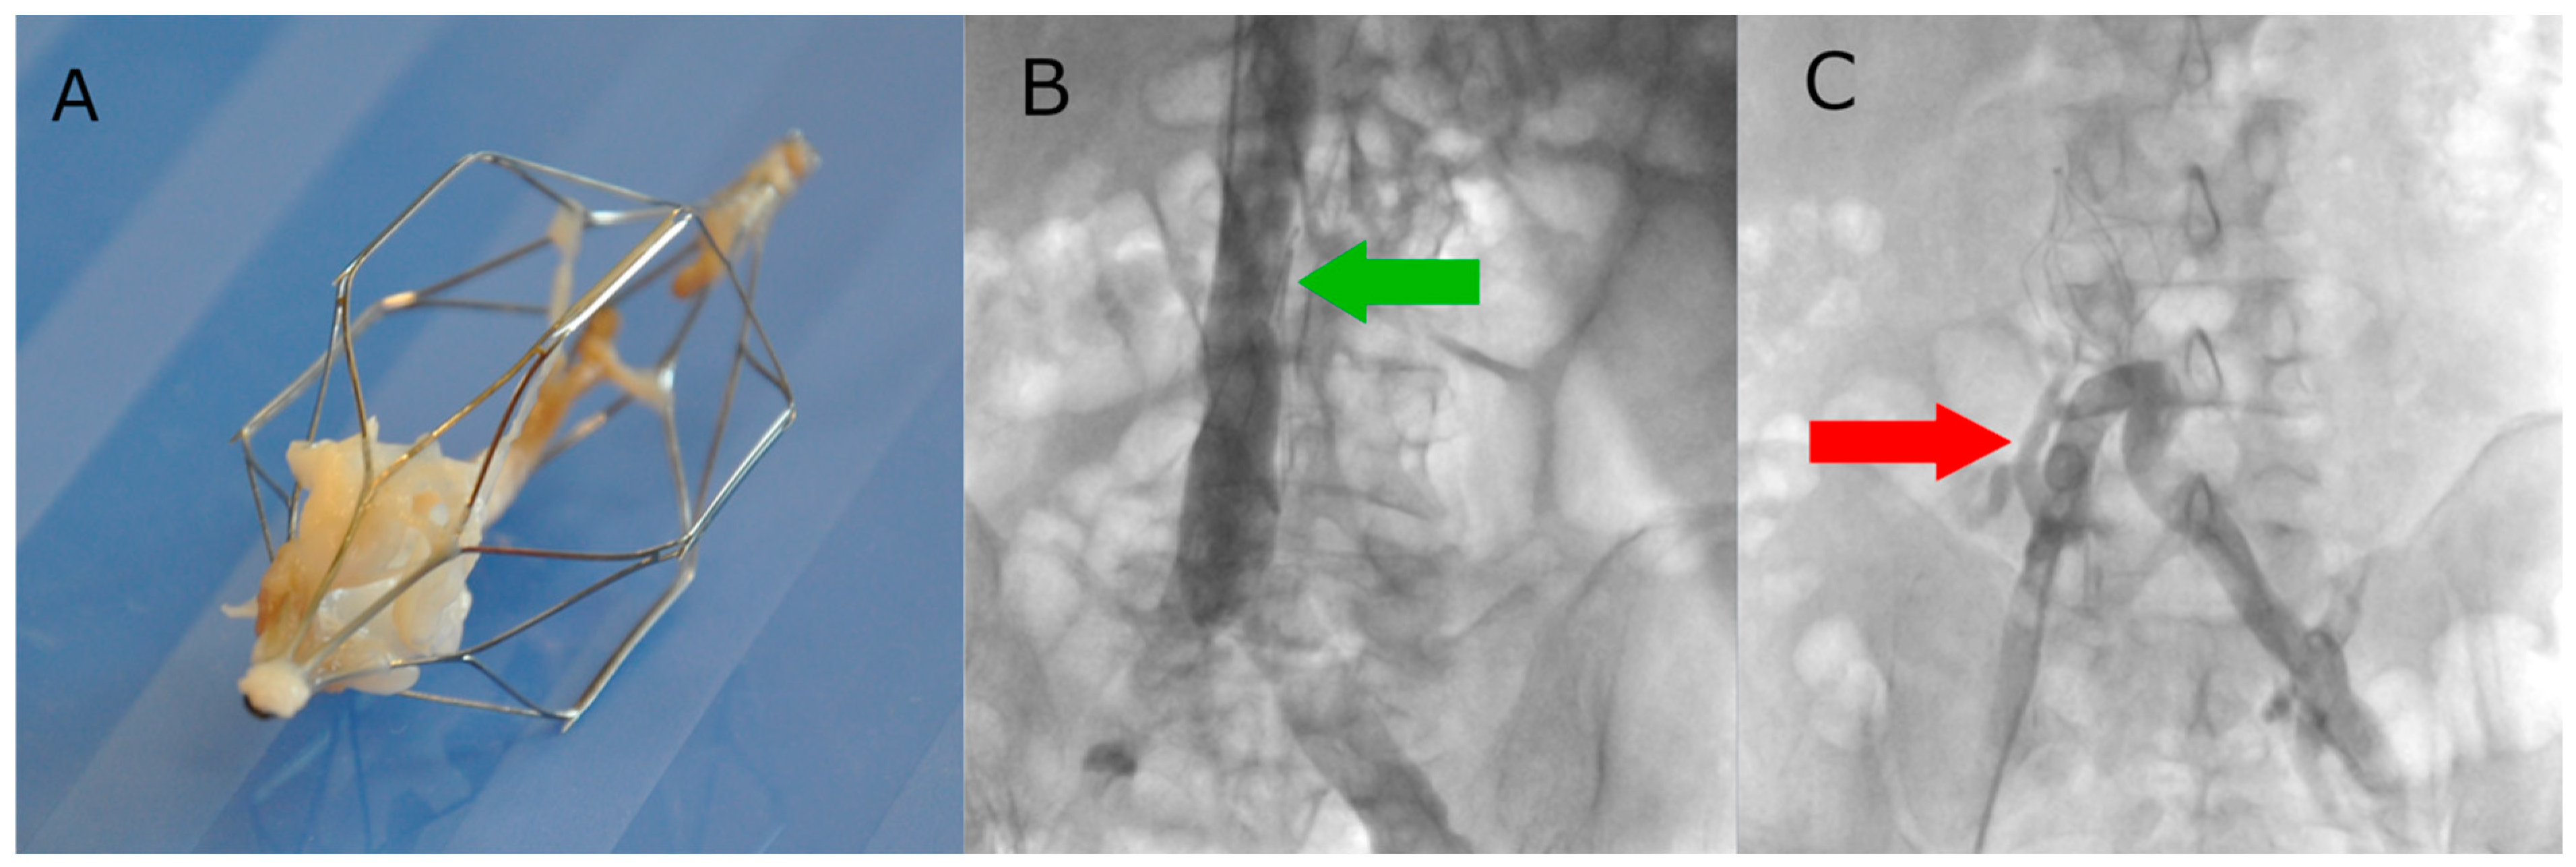

2.2. Procedural Details

| Abnormal findings during retrieval: | |||

| Thrombus at the top of the filter [n, %] | 2/13 (15.4%) | 33/83 (39.8%) | 0.124 |

| Apposition of the hook to the vessel wall [n, %] | 3/13 (23.1%) | 11/83 (13.3%) | 0.397 |

| Clotted filter [n, %] | 3/13 (23.1%) | 17/83 (20.5%) | 1.000 |